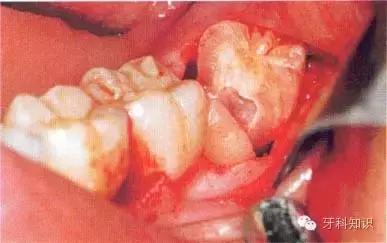

c使用纺锤形的车针( Komet - H162A.314),显露其最大周径至釉牙骨质界。车针末端应进入牙槽窝内壁

d 分牙前应认真确定分牙沟的位置:沿牙体长轴垂直(牙合)面至根分叉。用上述的车针分牙。切割至牙冠舌侧时应格外小心

e分牙已基本完成,远中牙片挺松后即可顺利取出